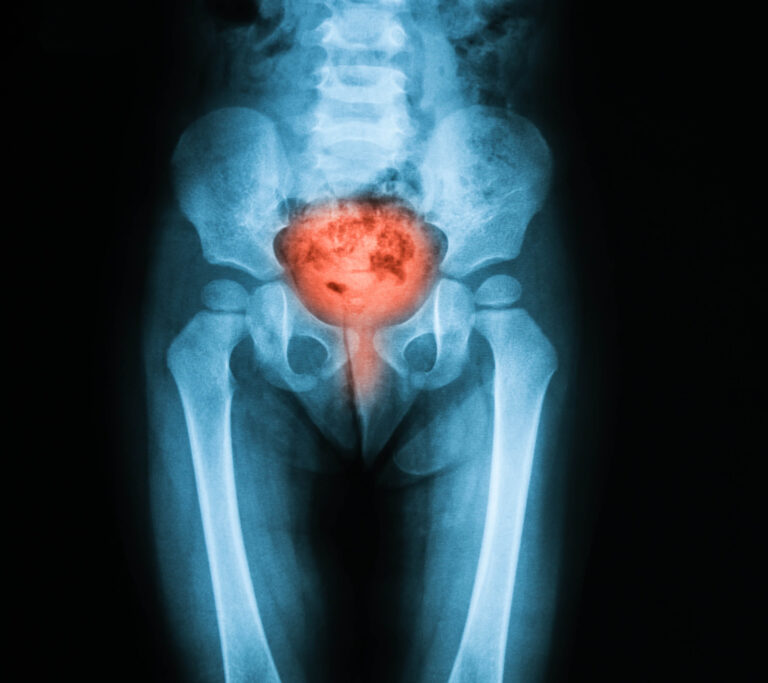

What Is Bladder Cancer?

Bladder cancer begins when cells in the bladder lining start to grow uncontrollably. Most cases are diagnosed at an early stage, when the disease is highly treatable. However, even early-stage bladder cancer may recur, which is why routine follow-up is essential.